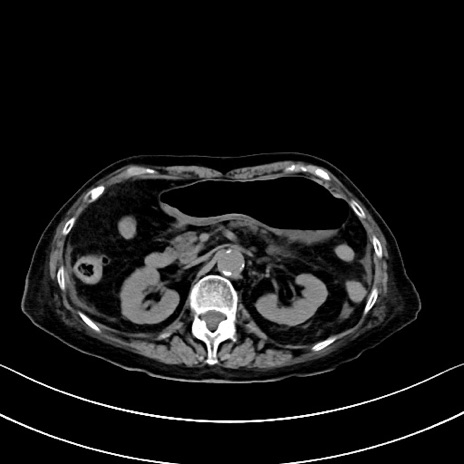

横断像